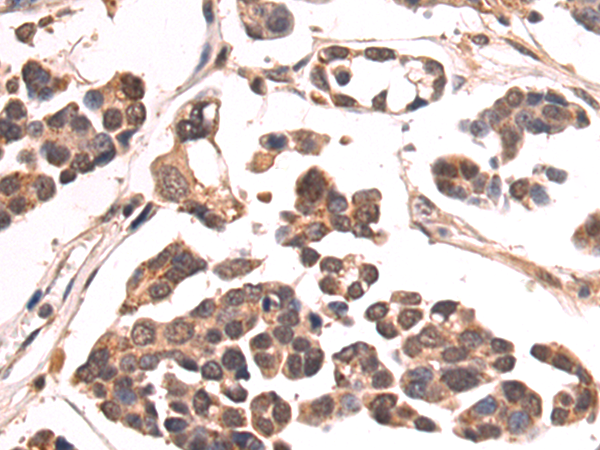

分类: 科研抗体货号: P07991别名: BB2; CD54; P3.58应用: WB,IHC反应种属: Human